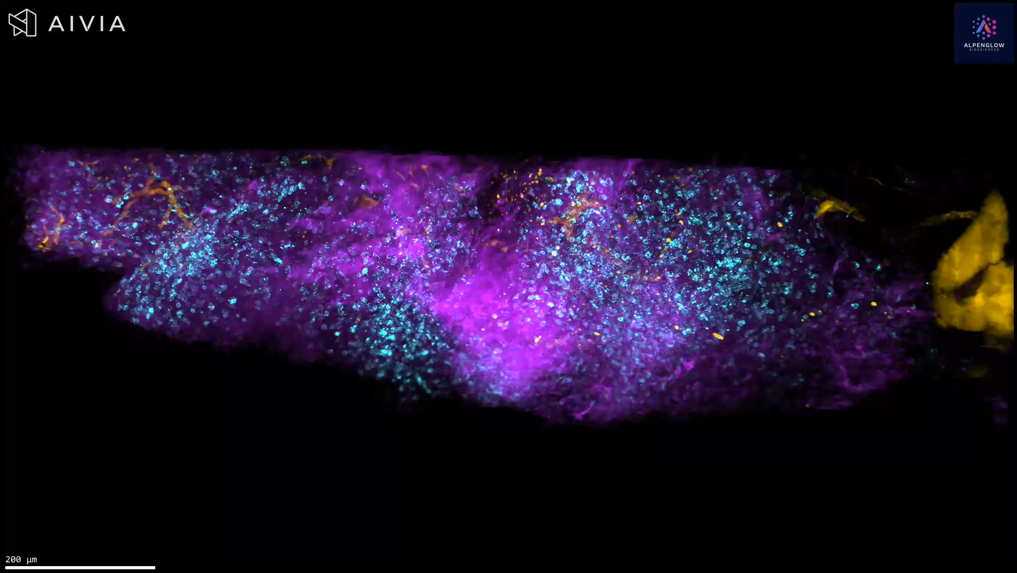

Unprecedented Detail in Atopic Dermatitis with 3D Imaging

Experience the power of 3D imaging in dermatology with this high-resolution video of an atopic dermatitis skin biopsy. Visualizing nerves (PGP9.5), immune cells (CD45), and nuclear structures (TOPRO3) in true spatial context, this technology reveals details impossible to capture with traditional tissue sections—offering unprecedented clarity and quantifiable insights for research.

Lymphocytes Cluster Near Nerves in Atopic Dermatitis

Delve into the intricate details of a lesional atopic dermatitis sample captured with cutting-edge 40X high-resolution 3D imaging. The sample is vividly stained with TO-PRO-3 blue for nuclei, PGP 9.5 white for nerves, and CD45 yellow for lymphocytes. Marvel at the precise preservation of epidermal and dermal structures and the clear visualization of immune-cell clusters in close proximity to specific nerve fibers.